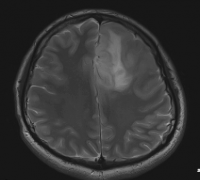

儿童高级别脑干胶质瘤存活率,脑干胶质瘤不像其他部位的胶质瘤那样根据国际卫生组织对中枢神经系统肿瘤的分类进行分类,而是根据磁共振T1和T2加权成...

在大多数研究中,脑干胶质瘤的治疗决策仅基于磁共振成像特征,不包括组织病理学诊断。因此,一些作者报道了位于髓质上方的全部弥漫性脑干胶质瘤表...

在儿童中,脑干神经胶质瘤占脑瘤的10%,并且这些通常被分为三个主要组。较大的亚组是弥漫性内在脑桥神经胶质瘤,其特征是在磁共振成像(MRI)上脑干的...